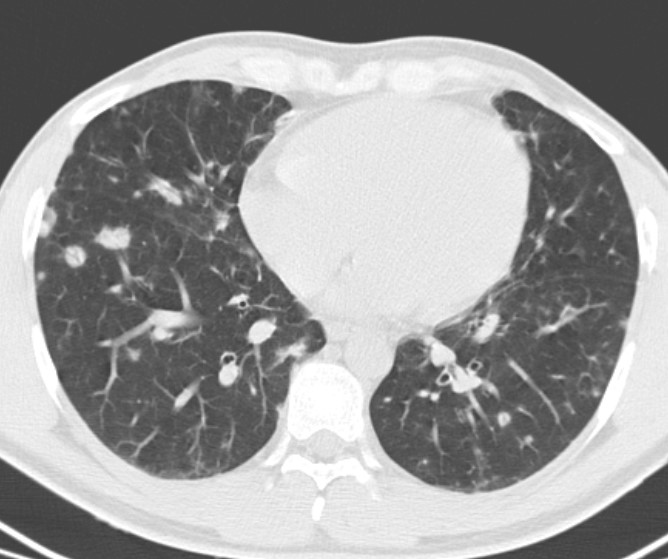

2. Рис. 1b. КТ органов гр. клетки у пациента с ОВИН. Figure 1b. Computer chest tomography of patient with common variable immunodeficiency | |